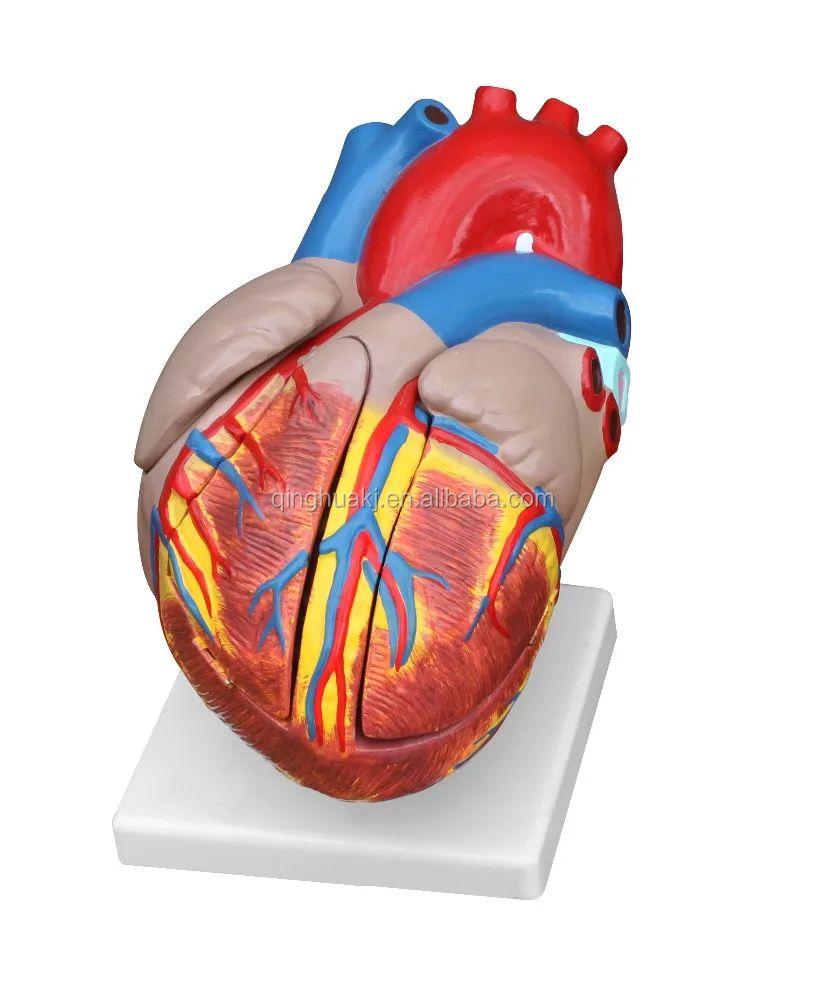

Фотографии и 3D-модели анатомии сердца человека